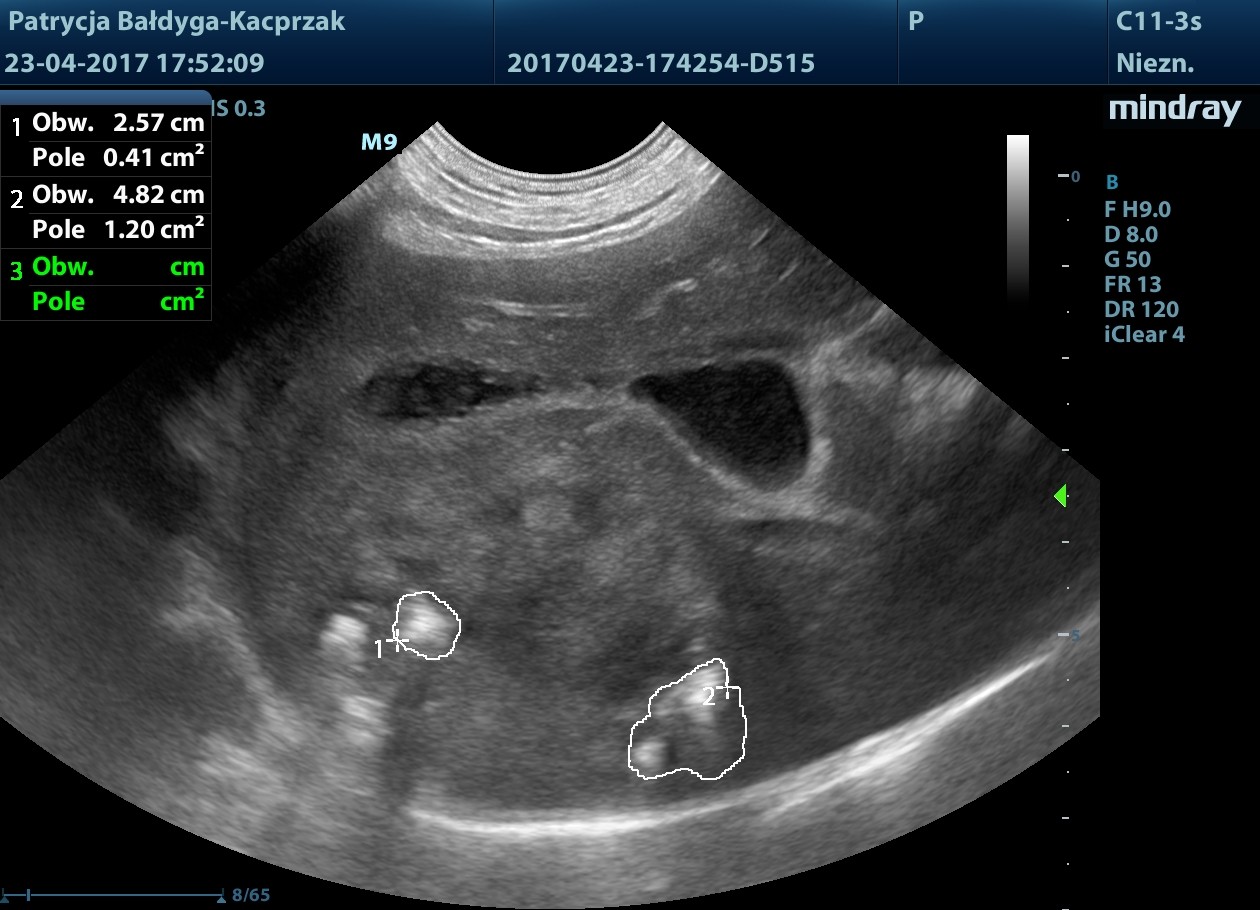

pod pęcherzykiem żółciowym zmiana ok 4,5 cm z drobnymi obszarami hiperechogennymi, jak zwłóknieniowymi/mineralizacyjnymi, gazem?

obrys 1- tu lekki cień akustyczny świadczący o twardości zmiany, obrys 2- tu artefakt rewerberacji, mogący sugerować obecność pęcherzyków gazu